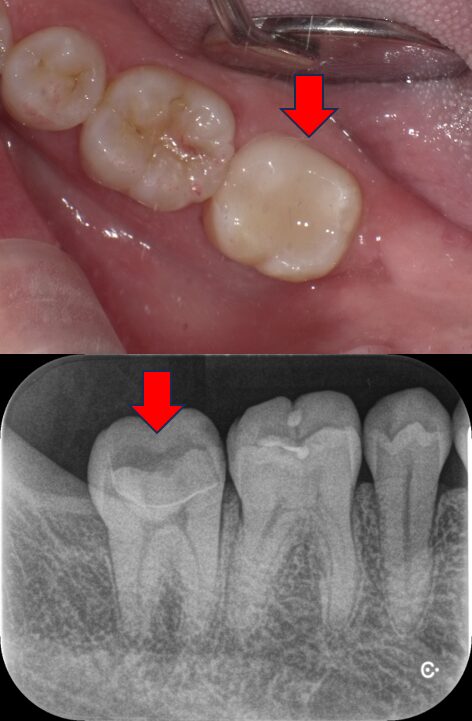

つくば市在住、「神経を残したい」深い虫歯を1回でセラミック修復治療した症例|40代男性・セレック治療

Before

After

| 主訴 | 歯がしみる 神経をなるべく残したい |

| 診断名 | 深い虫歯(象牙質う蝕・C2) |

| 治療方法 | セレックシステムによるセラミック修復 |